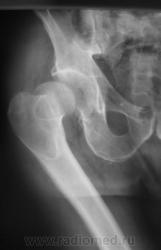

Пациент доставлен "по ургенту", направлен на рентгенографию тазобедренного сустава.

Крайне редкое наблюдение. Но переломов  вроде не видно... Непонято где головка - спереди или сзади, но вероятно куда то заскочила...

Возможен перелом дна вертлужной впадины.

Действительно, интересно где головка. Положение бедра как понимаю вынужденное.

"Газ" как-будто имеет продолжение назаднюю стенку впадины.

Думаю вывих в сравнении с таким переломом доминирует.

Может вывих с отрывом связки удерживающей головку во впадине?

Вывих наружу и назад с ротацией бедра большим вертелом вперед, отрыв собственной связки бедра с перелом в месте ее прикрепления; газа...увы....нет. Интересен механиз возникновения. Нельзя ли пару слов по обстоятельствам получения подобного повреждения. Предполагаю - падение с высоты на бок.

Ясно, таз был относительно фиксирован на сидении, бедро "выворачивало" вперед и снаружи- внутрь...очевидно....вот и вырвало из вертлужной впадины.

Скажите пож-та, нет ли на данном снимке правого тазобедренного сустава патологии до аварии? Меня заинтересовал шеечно-диафизарный угол, он очень острый и большой вертел, он какой-то поротичный. Может моё мнение ошибочно? Перелома здесь не вижу. С уважением Игорь Артурович.